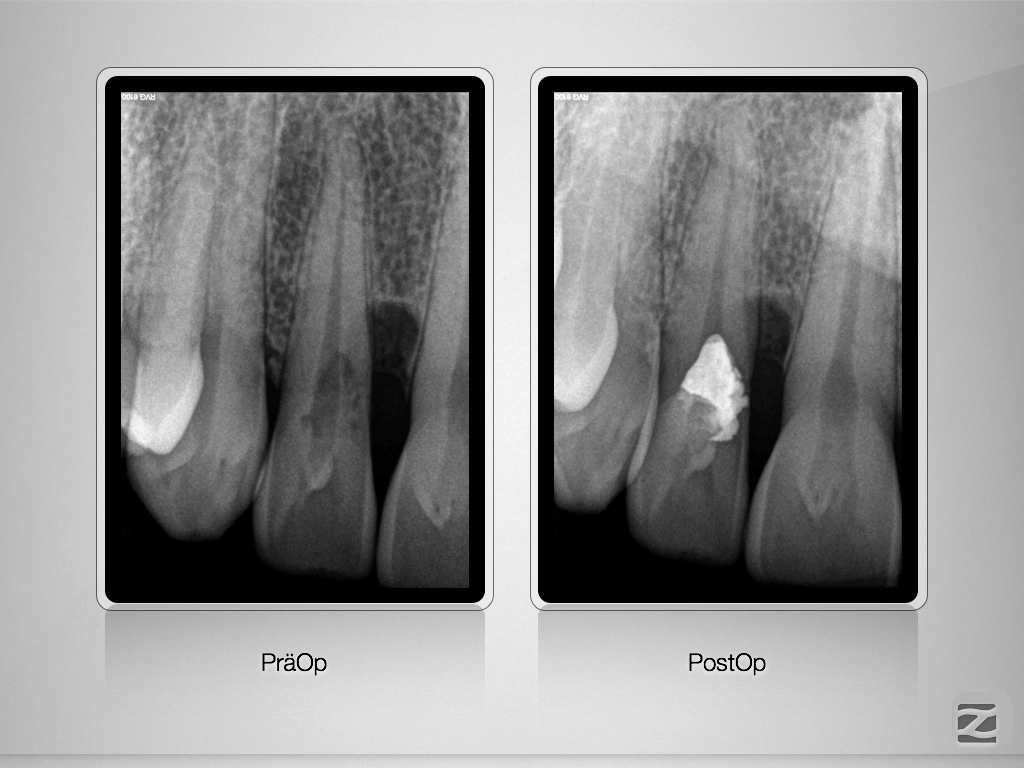

Externe Resorption mit Perforationen